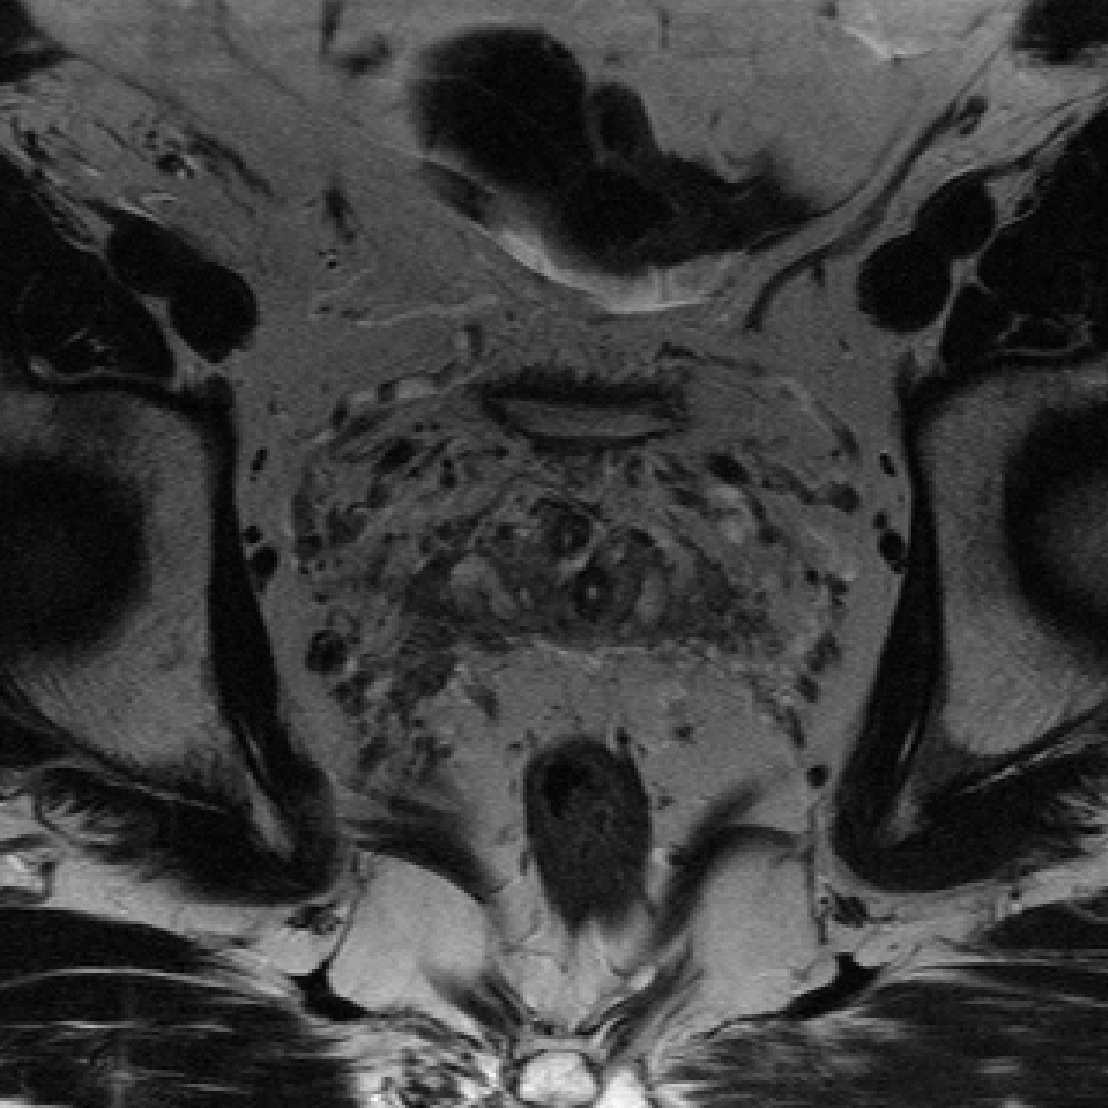

fastMRI prostate T2.

Originally, each volume of the fastMRI prostate T2 dataset contains three averages \citeptibrewalaFastMRIProstatePublicly2023: two averages sampling the odd k-space lines and one average sampling the even k-space lines. Then, for each average the authors estimate the missing k-space lines with GRAPPA \citepgriswoldGeneralizedAutocalibratingPartially2002a and perform SENSE \citeppruessmannSENSESensitivityEncoding1999a reconstruction. The final ground truth image is then obtained by taking the mean across the three averages (see code in the paper’s GitHub repository). However, we convert the data as follows: we take the raw k-space and average the two averages corresponding to the odd k-space lines and then fill the missing even k-space lines with the average corresponding to the even k-space lines. This k-space serves as our k-space data. We then take this k-space and apply a 2D-IFFT and finally perform a RSS reconstruction and use this image as ground truth.